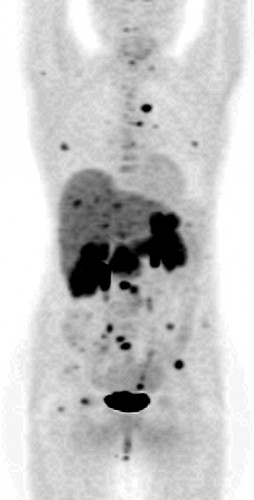

| Метастазы нейроэндокринной опухоли | Норма |